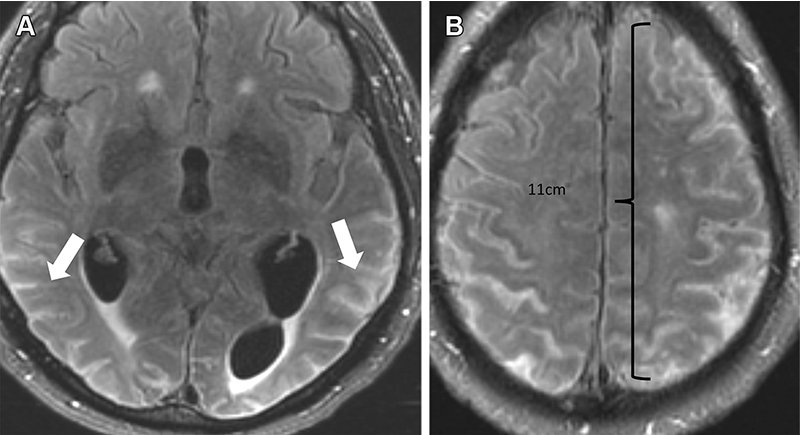

ARIA-e (effusione) grave in un 76enne con peggioramento del mal di testa, che riceveva aducanumab. Le immagini di MR cerebrale assiale del dicembre 2021 (3 settimane dopo la dose completa) mostrano essudati multifocali lungo il solci con iperintensità FLAIR (frecce in A), di più di 10 cm (grave) con sottile miglioramento leptomeningeo (B). Il trattamento è stato sospeso e, dopo l'interruzione della terapia, è stata osservata la risoluzione completa dell'effusione.